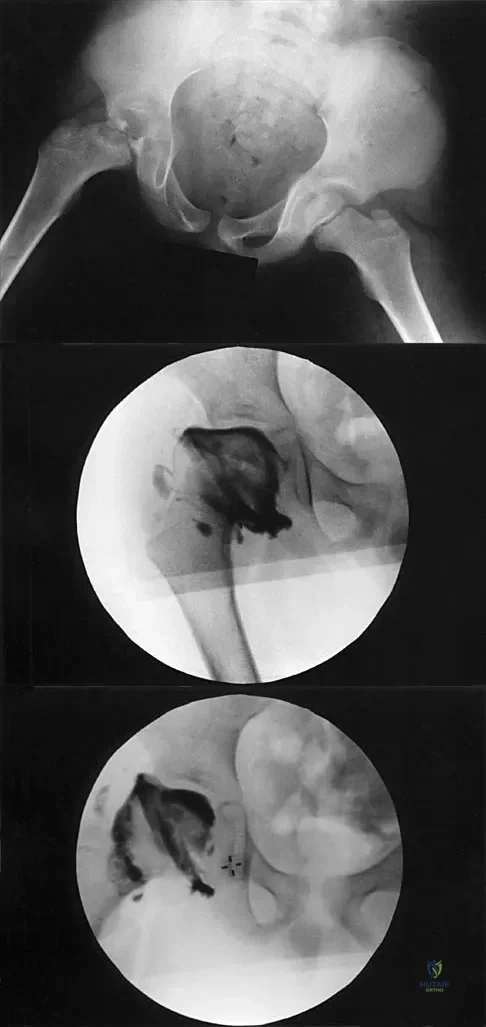

A 7-year-old patient has had a painless limp for several months. Examination reveals pain and spasm with internal rotation, and abduction is limited to 10 degrees on the involved side. Management consists of 1 week of bed rest and traction, followed by an arthrogram. A maximum abduction/internal rotation view is shown in Figure 40a, and abduction and adduction views are shown in Figures 40b and 40c. The studies are most consistent with

The radiographs show classic hinge abduction. The diagnostic feature is the failure of the lateral epiphysis to slide under the acetabular edge with abduction, and the abduction view shows medial dye pooling because of distraction of the hip joint. Persistent hinge abduction has been shown to prevent femoral head remodeling by the acetabulum. Radiographic changes are characteristic of severe involvement with Legg-Calve-Perthes disease.The Catterall classification cannot be well applied without a lateral radiograph, but this degree of involvement would likely be considered a grade III or IV. Because the lateral pillar is involved, this condition would be classified as type C using the Herring lateral pillar classification scheme.